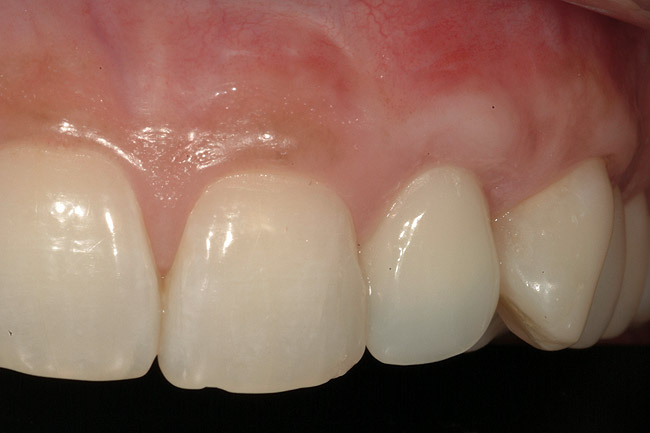

Figure 8  Marginal and papillary gingival contours were well preserved using this technique.

Figure 8

From a clinical perspective, the primary challenge was the development of an esthetic emergence of the dental implant-supported crown restoration. Maintenance of the soft-tissue dimensions, therefore, was critical to the treatment success. In an effort to optimally maintain the ridge form, a connective tissue graft harvested from the palate39,40 was placed over the collagen membrane to augment the soft tissues. Then, the buccal flap was advanced to achieve primary closure. Postoperative healing proceeded uneventfully. The overlying soft tissue exhibited rapid clinical closure and healed with minimal evidence of the surgical procedure. The clinical outcome was also consistent with development of the desired ridge form. Cone-beam computed tomography imaging revealed an alveolar ridge form that was optimal for implant placement at 5 months post-treatment. The radiographic density of the augmented region was similar to the adjacent native bone, with no discernable interface between native and apparent new bone, consistent with integration and remodeling. Surgical re-entry for implant placement revealed the optimal ridge form (Figure 6 ). The implant was allowed to integrate for 5 months prior to the healing abutment placement and interim restoration. The overcontoured soft tissues enabled surgical sculpting to achieve the desired contour for the restorative emergence. A highly acceptable esthetic result was achieved. With preservation of the marginal and papillary gingival contours (Figure 7 and Figure 8 ); the radiographic presentation was consistent with normal bone remodeling and implant integration.